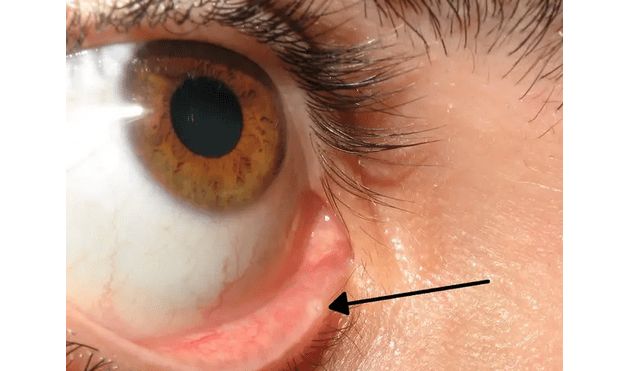

Všimli ste si, že na spodnej časti viečok sa nachádzajú malé dierky v rohu? A rozmýšľali ste načo vlastne slúžia? Nuž, nachádzajú sa na oboch viečkach a sú akýmsi lievikom, ktorý umožňuje slzám, ktoré sa nekotúľajú dole lícam, „cestovať“. Skončia napokon až vo vašom nose, čo vysvetľuje aj to, prečo si pri plači musíte fúkať nos.

Táto malá dierka sa odborne nazýva aj slzný bod. Je to v podstate tak, že dôvod prečo počas alebo po plači si potrebujete vyfúkať nos, je ten, že tekutiny sa dostávajú cez túto dierku priamo do nosa. Všetky slzy, ktoré sa neskotúľali dole lícami sa teda dostanú do slzného bodu. Tekutina sa následne odvádza cez nasolakrimálny kanál. A ak ste si ešte tieto malé dierky nevšimli, utekajte sa pozrieť do zrkadla.